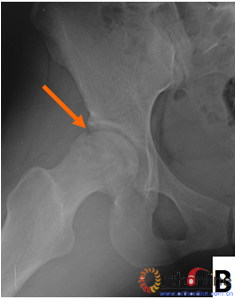

图2 依据股骨头外侧柱存留情况,股骨头坏死的分型。(图2-1)分为Ⅰ型(外侧柱全部存留)(A)MRI图像显示;(B)7年后CT显示股骨头仍未塌陷;(图2-2)Ⅱ型(外侧柱部分保留)(A)MRI显示外侧皮质存留;(B)4年后CT显示股骨头仍未塌陷;(图2-3)Ⅲ型(坏死带穿透股骨头);(A)MRI显示坏死带;(B)2年后股骨头塌陷

Fig 2 According to preservation of the lateral pillar, the necrosis was divided into three types. (Fig 2-1)Type Ⅰ: Whole lateral pillar preserved (A) MRI showing; (B) no collapse occurred seven years later by CT showing. (Fig 2-2)Type Ⅱ: Preservation of the partial lateral pillar, (A) MRI showed the preservation of the lateral cortical bone; (B) no collapse of the femoral head four years by CT. (Fig 2-3)Type Ⅲ: the necrotic line pass through the cortical bone and bone morrow ;(A) MRI showed the necrotic line; (B) collapse of the femoral head occurred two year later.